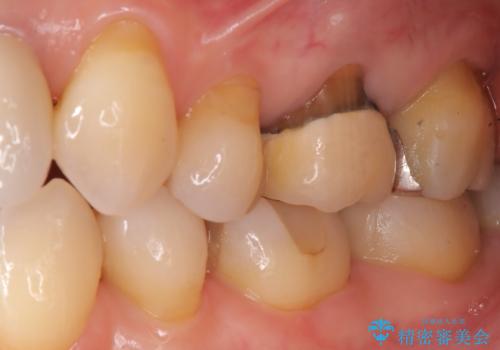

- 「以前治療した被せ物の色が気になる」「最近しみるようになった」との主訴で来院されました。診察の結果、古い被せ物の周囲に段差ができており、そこから虫歯が進行している状態でした。また、色も経年劣化により周囲の歯と調和が取れておらず、笑ったときに目立つとのお悩みもありました。

被せ物の下の虫歯を除去し、必要に応じて土台の補強を行ったうえで、見た目が自然で長期的な安定性もあるセラミッククラウンによる修復をご提案しました。見た目と機能の両方を改善するため、隣接する歯との色調や形態のバランスも考慮した治療計画を立てました。

まず古い被せ物を慎重に取り除き、中に広がっていた虫歯を丁寧に除去しました。歯質の状態を確認したうえで、必要な部分には土台(コア)を補強し、セラミッククラウンを装着する準備を整えました。

最終的な被せ物には、周囲の歯と自然になじむような色合い・透明感を持つセラミックを採用。形も元の歯に近づけ、違和感のない見た目と噛み心地を再現しました。